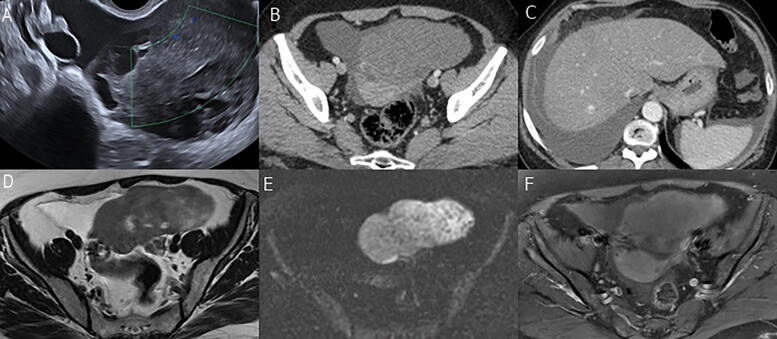

Introduction: Ovarian fibrothecoma is a rare benign sex cord-stromal ovarian tumor sorted under the thecoma-fibroma group. We present an analysis of clinical and laboratory findings and the radiological characteristic features of pathologically proven fibrothecomas in variable imaging modalities.

Methods: A retrospective analysis was done for 88 patients with 90 pathologically proven ovarian fibrothecoma between January 2011 and December 2023 from our center's prospectively maintained database. All the patients underwent preoperative ultrasonography, computed tomography (CT), and magnetic resonance imaging (MRI) scans, clinical examinations, basic laboratory tests, and tumor markers.

Results: The results of Spearman's correlation revealed a statistically significant positive correlation between the largest tumor diameter and serum level. CA 125, the degree of ascites, and diffusion weighted imaging (DWI) signal intensity while the results of point biserial correlation revealed a statistically significant correlation of the largest tumor diameter with the presence of ascites, cystic changes, abdominal enlargement, surgery type, and border type. There were also statistically significantly higher hypoechoic lesions in the smaller tumor group (p = 0.001) but not for isoechoic (p = 0.099) and mixed (p = 0.052). Regarding the MRI, there was a statistically significantly larger tumor diameter in T2 mixed-hyperintense versus hypointense (p = 0.007) and intermediate (p = 0.010) signal intensities.

Conclusion: Fibrothecoma showed a statistically significant positive correlation between the largest tumor diameter with serum level CA 125 and the amount of ascites. On imaging, it shows mild enhancement in both CT and MRI, with a statistically significant positive correlation of the largest tumor diameter with T2 and DWI signal intensity.